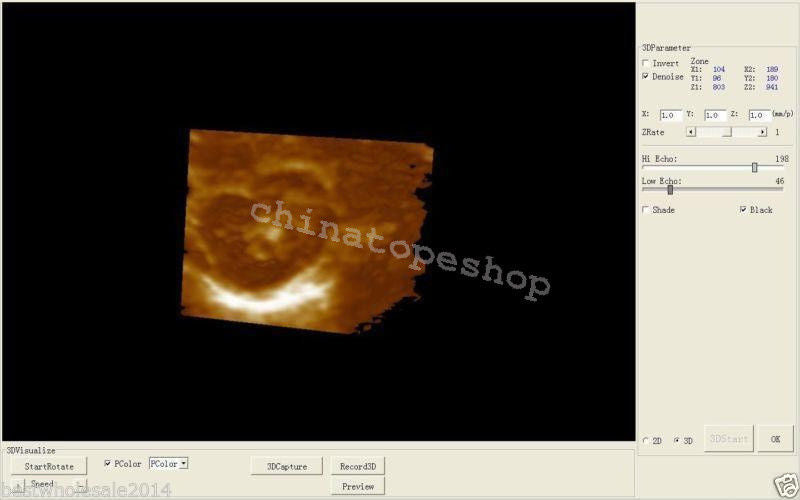

With the inclusion of a 3D workstation, the Laptop Ultrasound Scanner offers enhanced imaging capabilities that allow healthcare professionals to view detailed 3D images. This functionality improves diagnostic accuracy and helps in monitoring various conditions over time. Additionally, the software included enables efficient storage and easy retrieval of images, supporting medical professionals in their evaluations. Hence, this scanner not only provides high-quality imaging but also practical functionalities that are essential for modern medical practices.